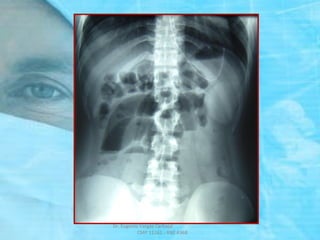

RADIOGRAFIA SIMPLE DE ABDOMEN

DE PIE Y DECUBITO

 Mejor valor diagnóstico.

 Se debe tomar en posición DE PIE

y DECUBITO, incluir diafragma

y pelvis.

 Rx. de PIE: NHA.

 Rx. de DECUBITO:

Gas Intraintestinal

ASAS YEYUNALES:

SIGNO

“PILA DE MONEDAS”

IMAGEN DE

“COLLAR DE CUENTAS” ó

“SIGNO DEL ROSARIO”

( PRE – OBSTRUCCION )

NIVELES HIDROAEREOS